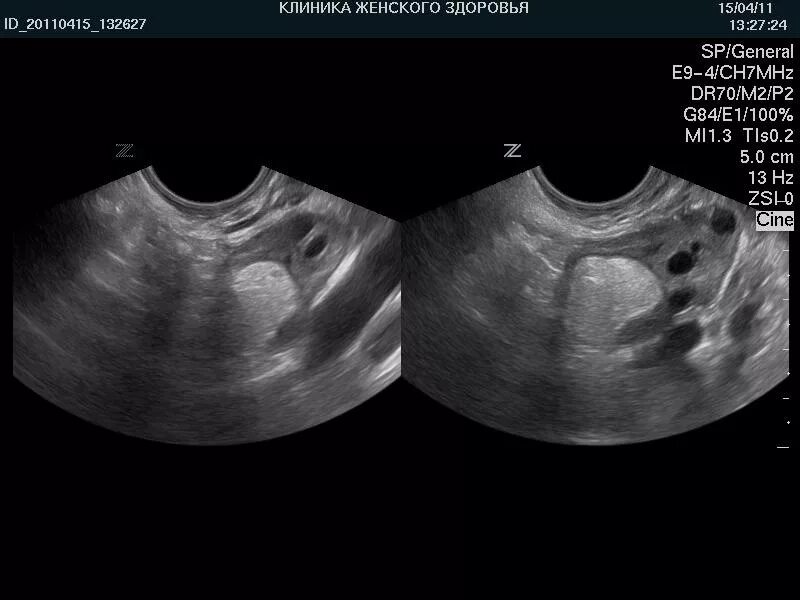

Объемные кистозные образования